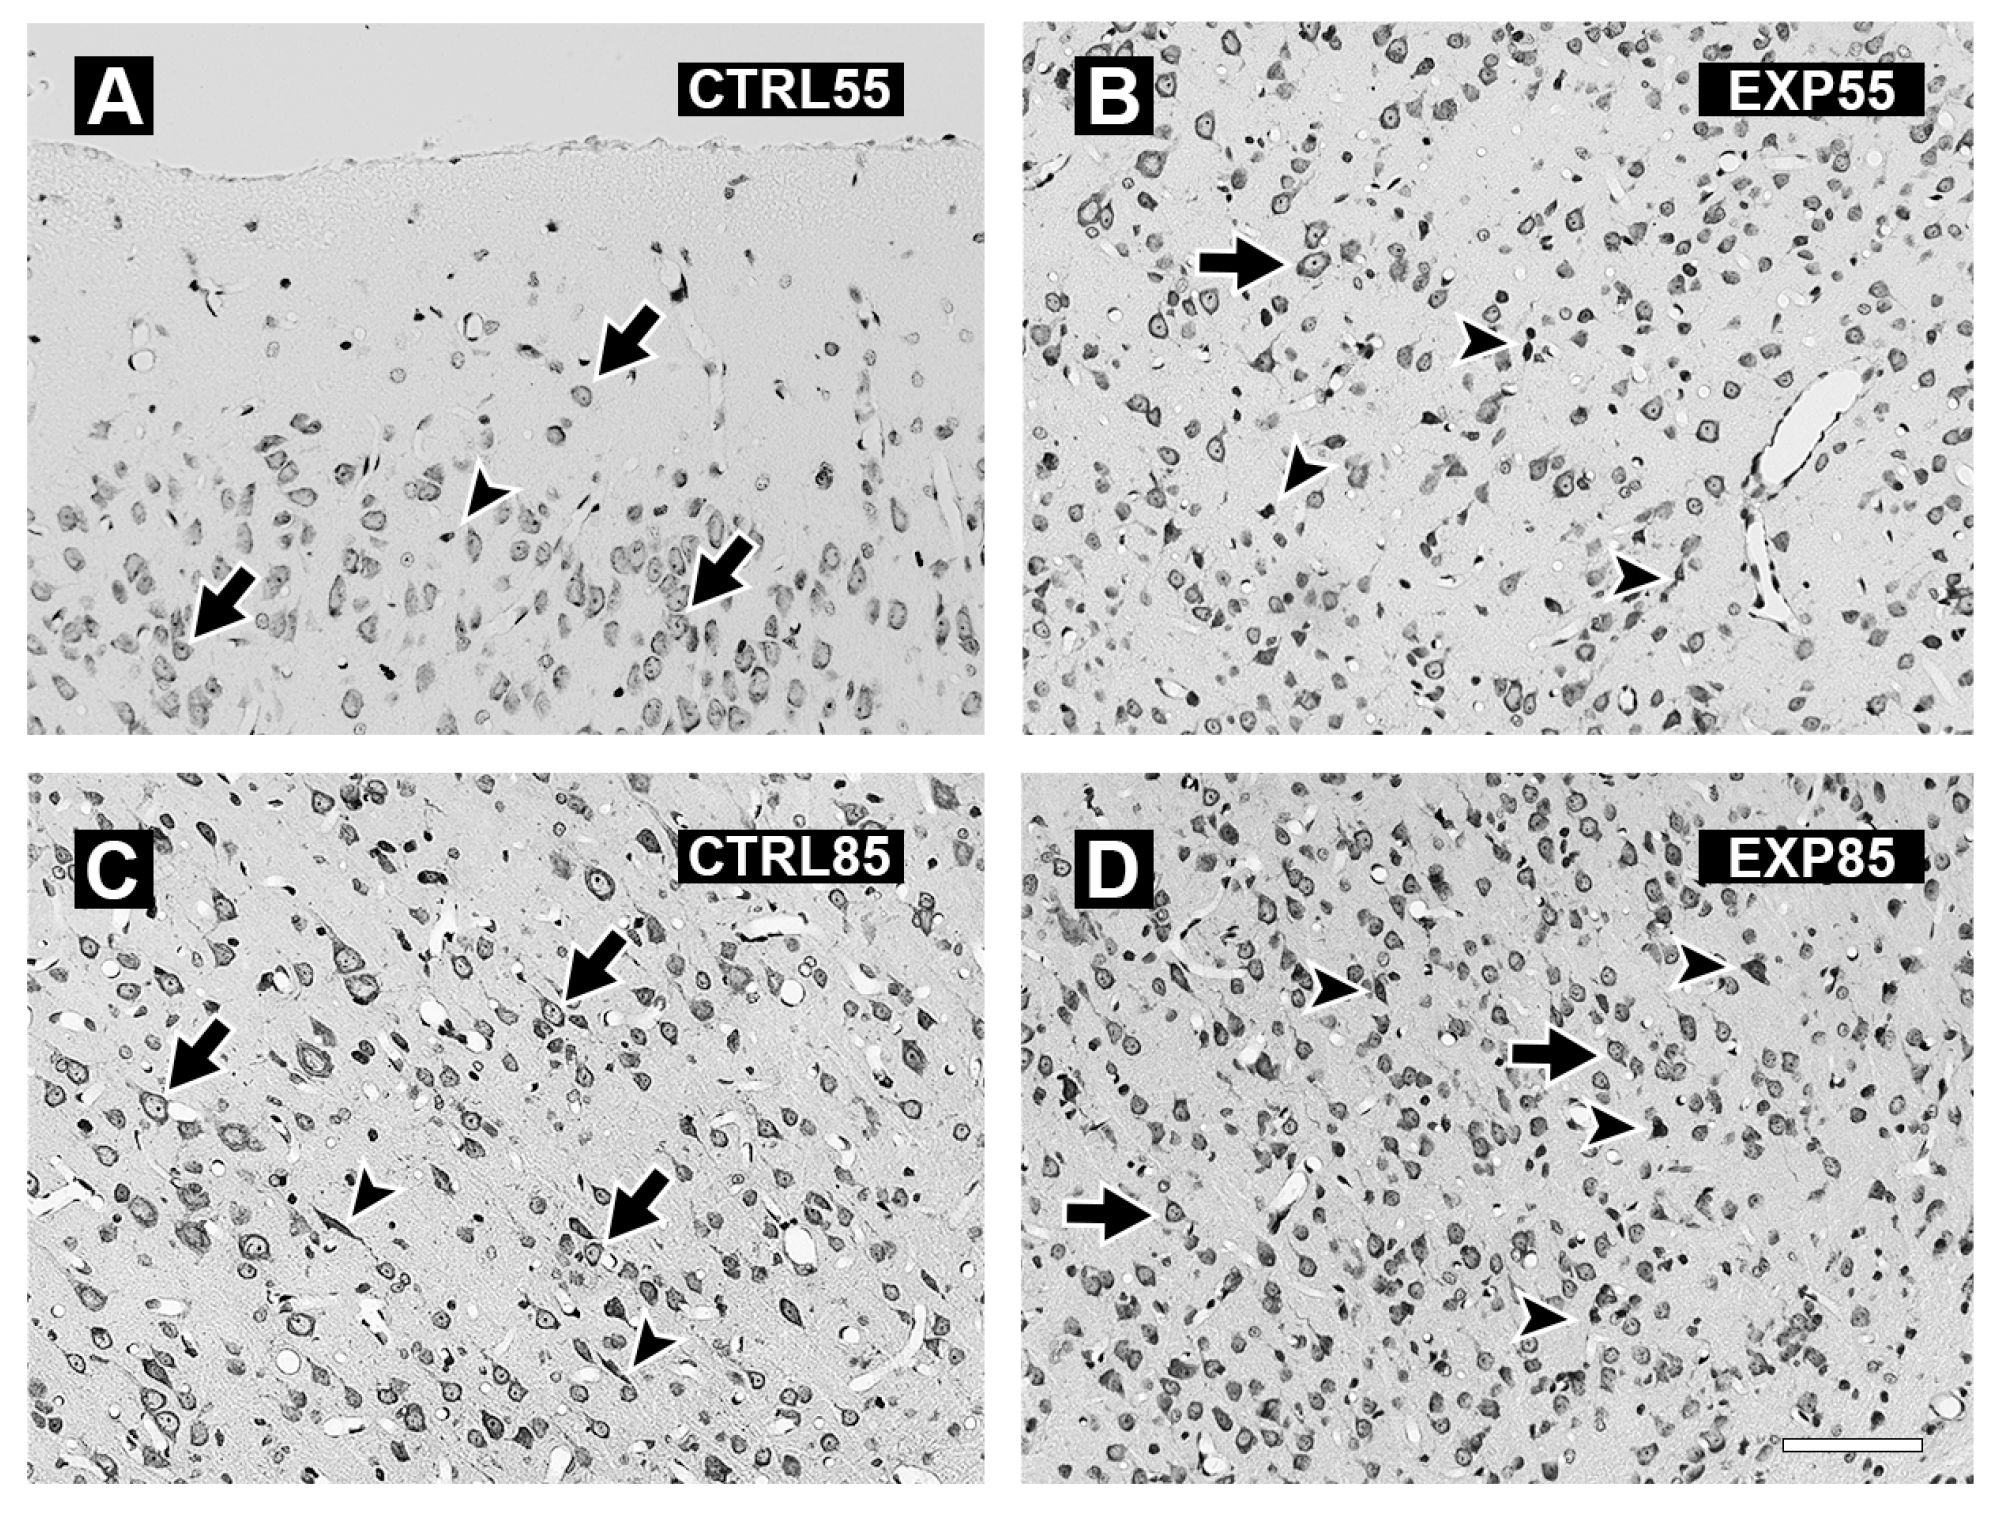

2.3. Histology

3. Results